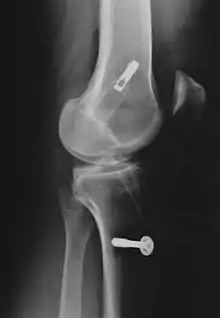

![]() Arthroscopic anterior cruciate ligament (ACL) reconstruction (right knee). The tendon of the semitendinosus muscle was prelevated, folded and used as an autograft (1). It appears through the remnant of the injured original ACL (3). The autograft then courses upwardly and backwardly in front of the posterior cruciate ligament (2). | |